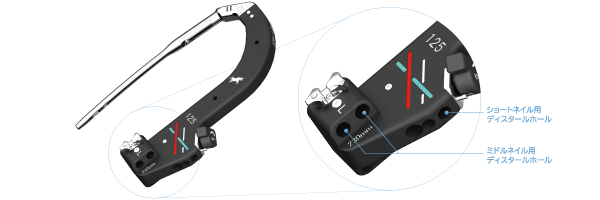

HTS Unicorn Nail 2

It is an implant that provides a variety of options for trochanteric fractures in developed countries with super-aging societies.

- Short Nail

- Middle Nail

- Single Lag Screw

- Double Lag Screw